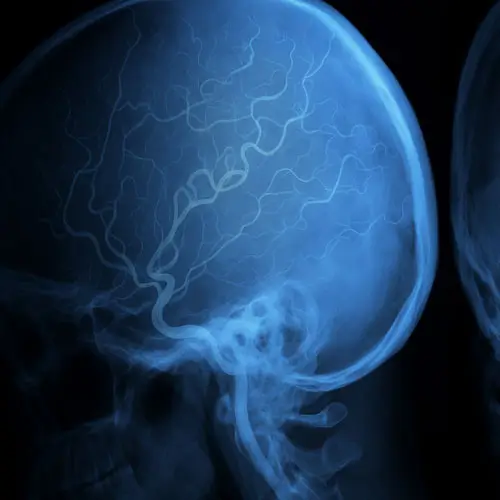

Angiografias Cerebrais

Exame de imagem que permite mapear, com alta definição, as artérias do cérebro e identificar alterações como aneurismas, malformações e estenoses.